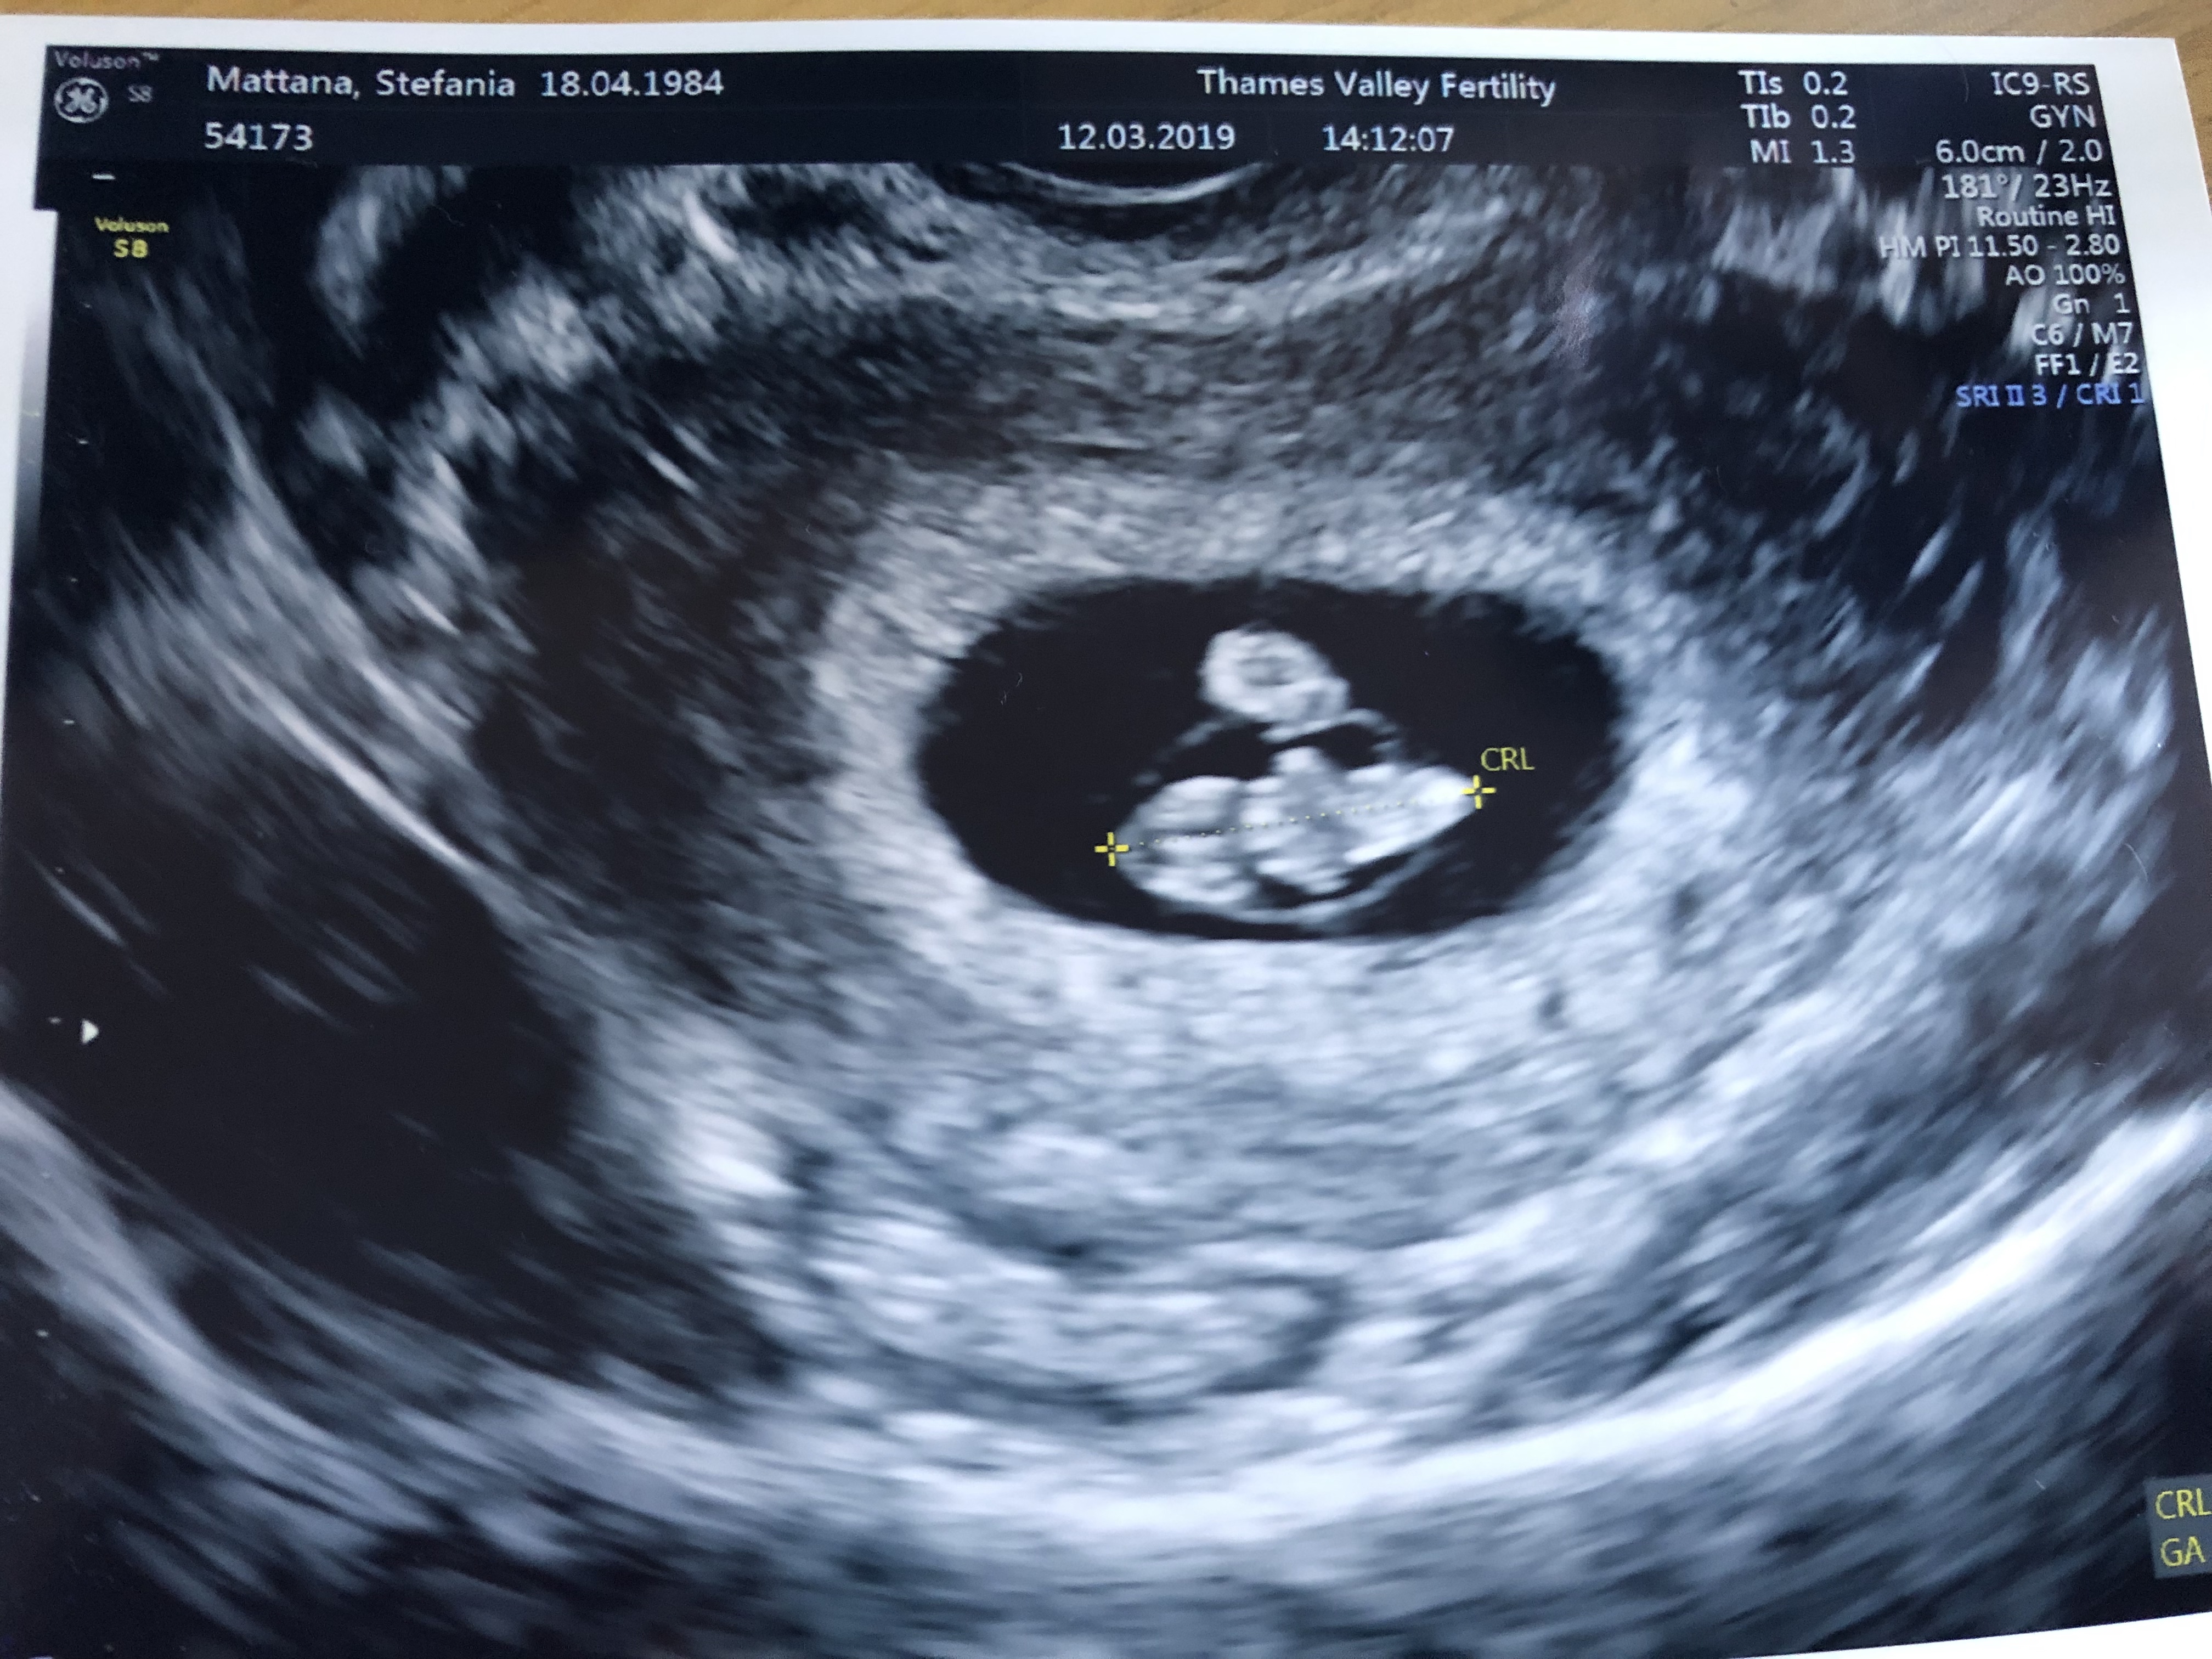

The fertility clinic discharged us with success – we’re now a “regular” expecting family! Before being discharged, the staff at the clinic performed an internal scan to make sure the cervix was well closed, and Frosty was there, alive and kicking.

That little ball is the yolk sac that is evolving into the placenta

Don’t they look like a legit snowman here? Snow angel the hell out of it, Frosty!

The sonographer was so skilled – and Frosty was so well placed in the womb – that not only did she manage to see the heart beating, but also she made us HEAR it! This is kind of unusual as you can hear the heartbeat at around week 10/12.